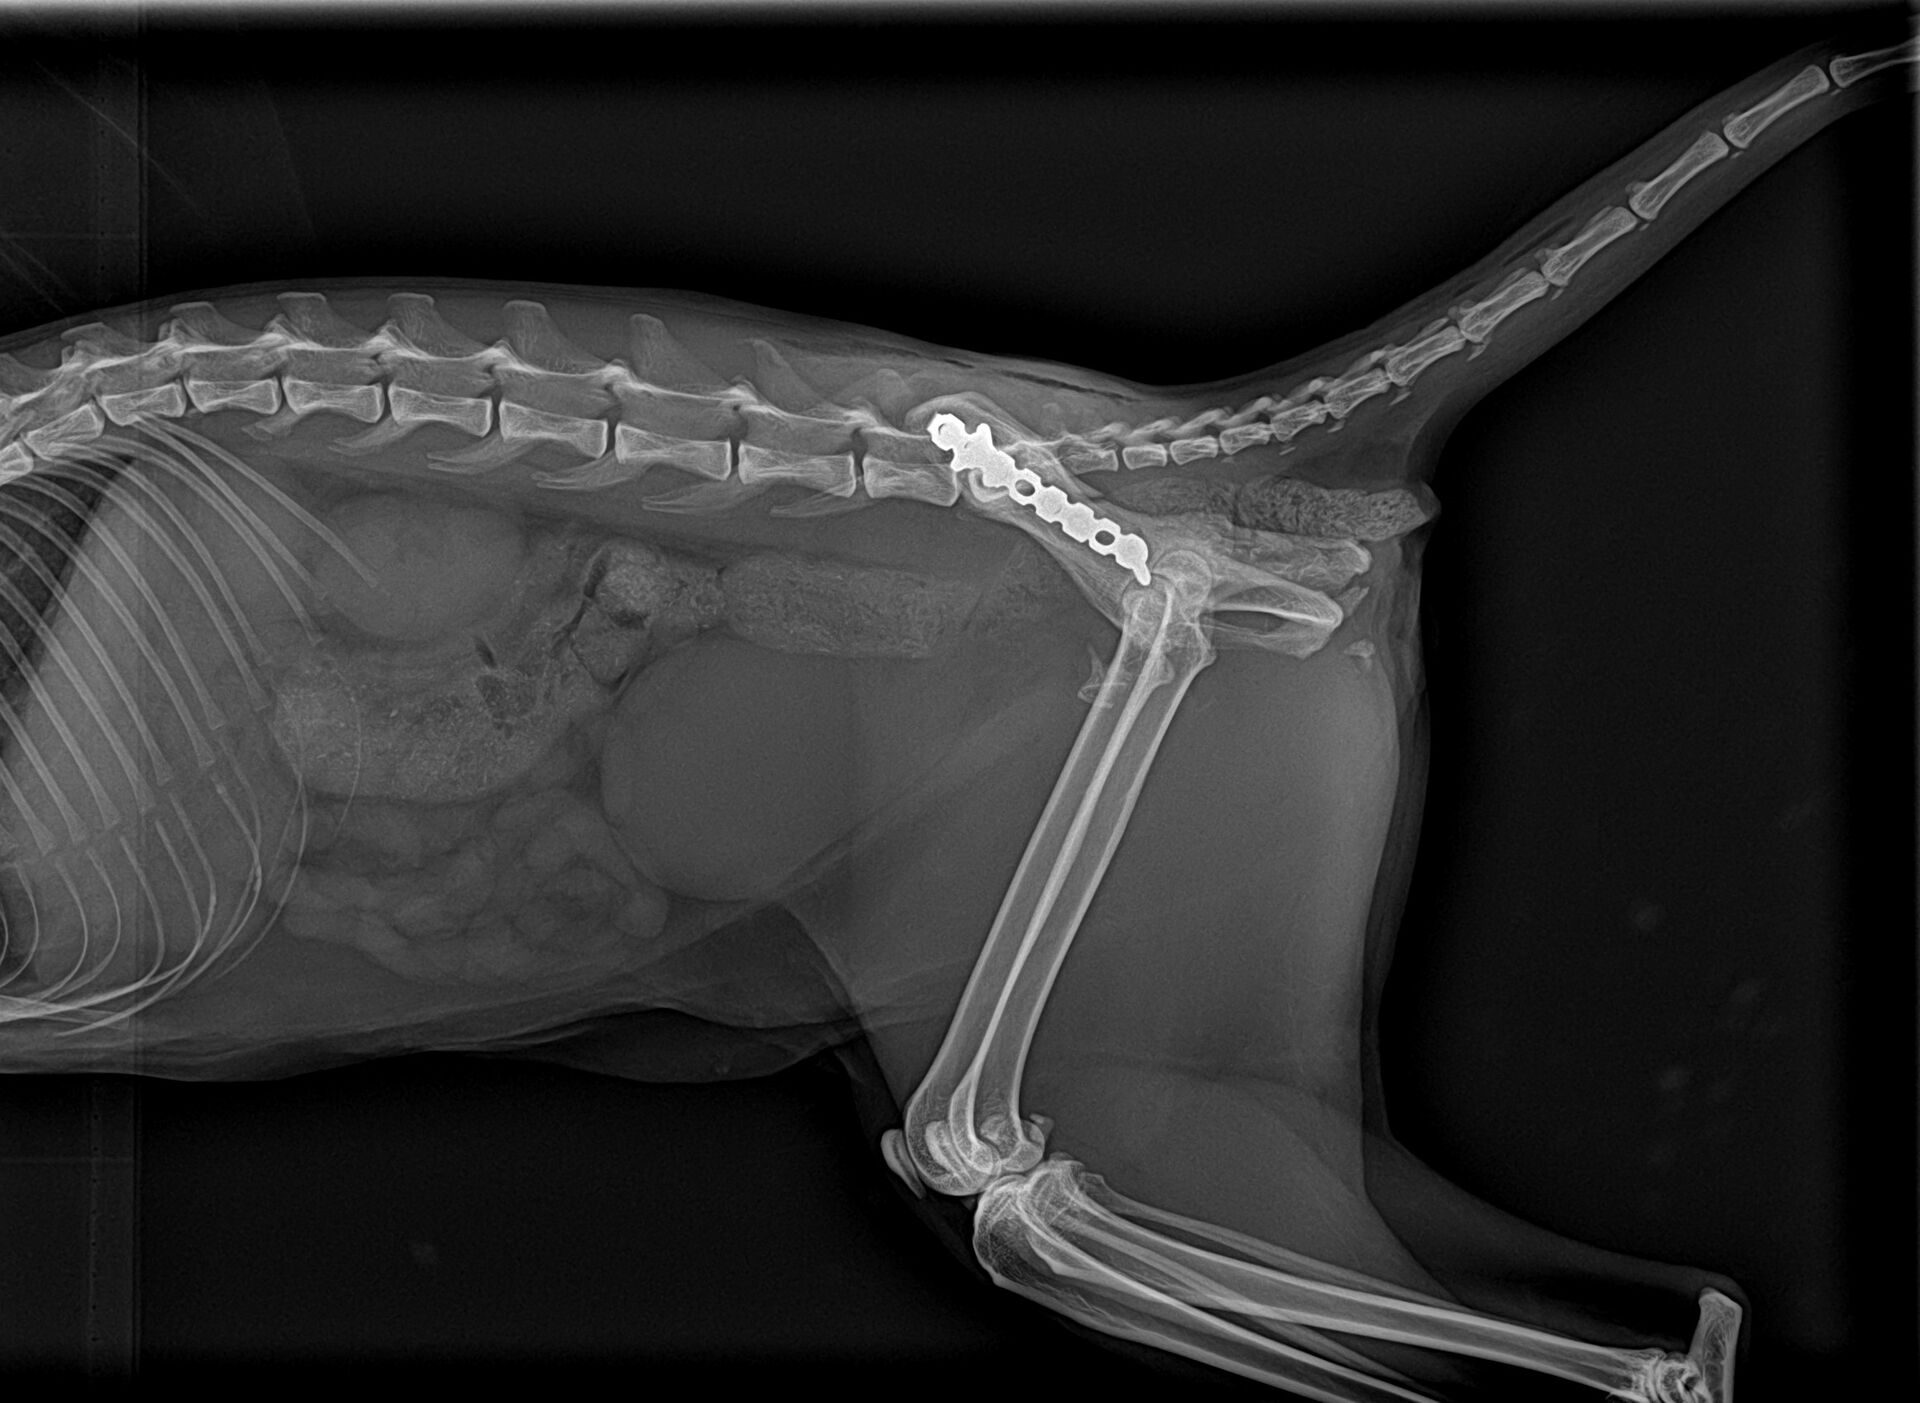

当日から2日間点滴したところ、後肢を動かし始めたので脊髄は問題ないと判断し、骨盤の整復術を行いました。その結果が以下の写真です。

骨盤整復はうまくいったのですが、右側の仙腸関節が脱臼していることが判明しました。スクリューなどの準備をして後日再手術をすることになりました。